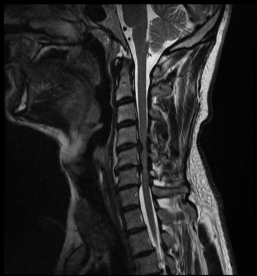

Spinalkanalstenose IISpinalkanalstenose III

MRI with lateral reconstruction of the cervical spine and a lateral postoperative radiographic check. On the left, an hourglass-shaped constriction of the spinal cord can be seen. The right image shows the condition after surgical decompression and stabilization.